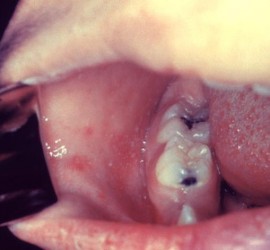

Характеризуя состояние слизистой оболочки протезного поля, Суппли выделяет четыре класса: Здоровая слизистая оболочка полости рта (умеренно податливая, умеренно подвижная, бледно–розового цвета). Атрофичная слизистая оболочка полости рта (малоподатливая, бледно–розового цвета, слабо увлажнена, с повышенной болевой чувствительностью); Слизистая оболочка с избыточной податливостью, чрезмерно увлажнена; Чрезмерно подвижная слизистая оболочка, расположена в области вершины […]